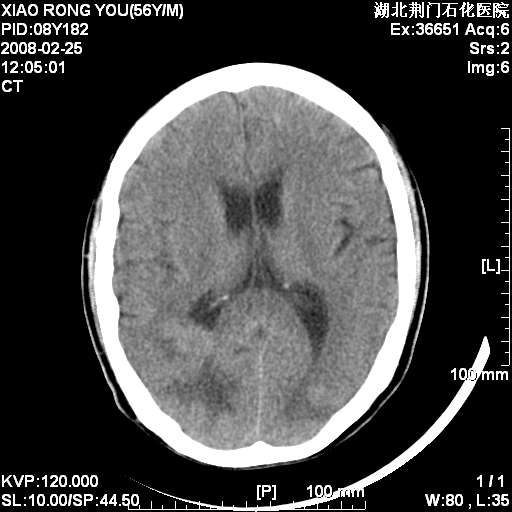

男性,68岁,多年肺结核病史。最近ct复查右肺有占位。

3天后增强

增强明显强化,转移?

如此血管样强化表现,转移瘤不好解释,考虑脑膜瘤或血管瘤

平扫无明显占位及水肿、增强扫描强化明显以血管瘤可能性大